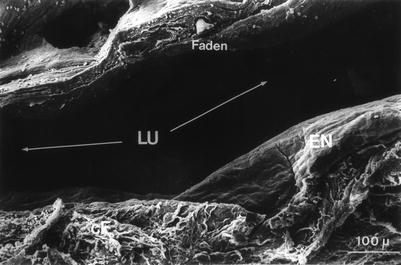

Between days 40 and 60, within the wall caverns appeared, together with a massive infiltration of activated lymphocytes, plasma cells, macrophages, and erythrocytes. The wall however remained stable because of the new endothelium and the subendothelial tissue containing a continuous basal membrane, structured collagen fibers type I, and differentiated muscle cells (Figs. 2.14, 2.15, and 2.16).

Fig. 2.14

Allogeneic abdominal thoracic duct graft of rat. 40 days after grafting (ultrathin section, 1000-fold magnification) (E endothelial cell, LU lumen, cF collagen fibers)

Fig. 2.15

Allogeneic abdominal thoracic duct graft of rat. 40 days after grafting (scanning electron microscopy, 440-fold magnification). LU lumen, EN endothelium, cF collagen fibers, Faden suture)